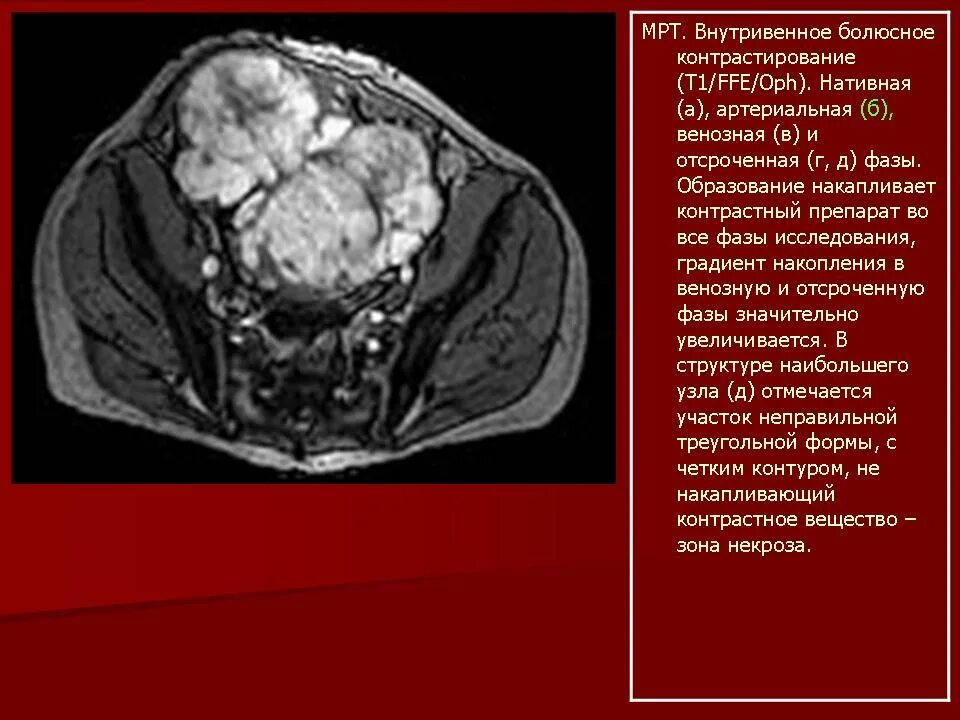

Забрюшинная онкология